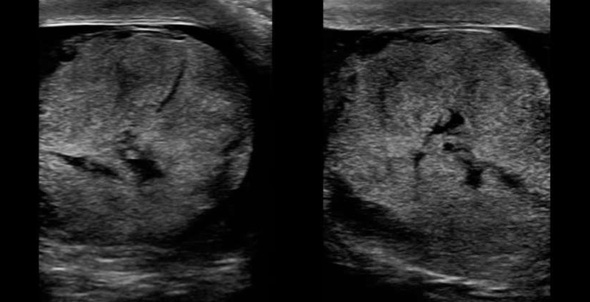

Figure 2. Also known as the ‘buddy’ or ‘spectacle’ view, a coronal scan showing both testicles side by side allows for comparison in size, relative echogenicity and blood flow.

- Sonographic findings can be variable depending on the duration of torsion and extent of vascular compromise. The testicle can appear enlarged and hypoechoic and the parenchyma of the testicle will become less homogenous when compared with the unaffected testicle. (Video 5) In advanced cases, testicle can look hyperechoic with areas of necrosis.

Video 5. Transverse scan of both testicles showing normal right testicle and left testicular torsion. Note the hypoechogenicity of the right testicle.